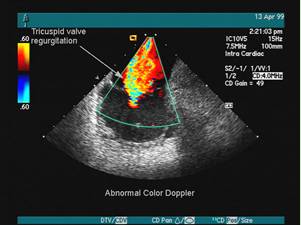

彩超并非是字面意义上的"彩色的B超",而是在普通B超的基础上出现了彩色-多普勒超声波探测诊断技术,会用彩色标注心脏、血流等指标,彩超观测到的图像以红蓝两色为主。

这种技术能够观测到胎儿的血液流动情况,有利于及时发现胎儿的异常。例如:胎儿颈部如有血流环,则意味着发生了可导致窒息死亡的脐带绕颈。